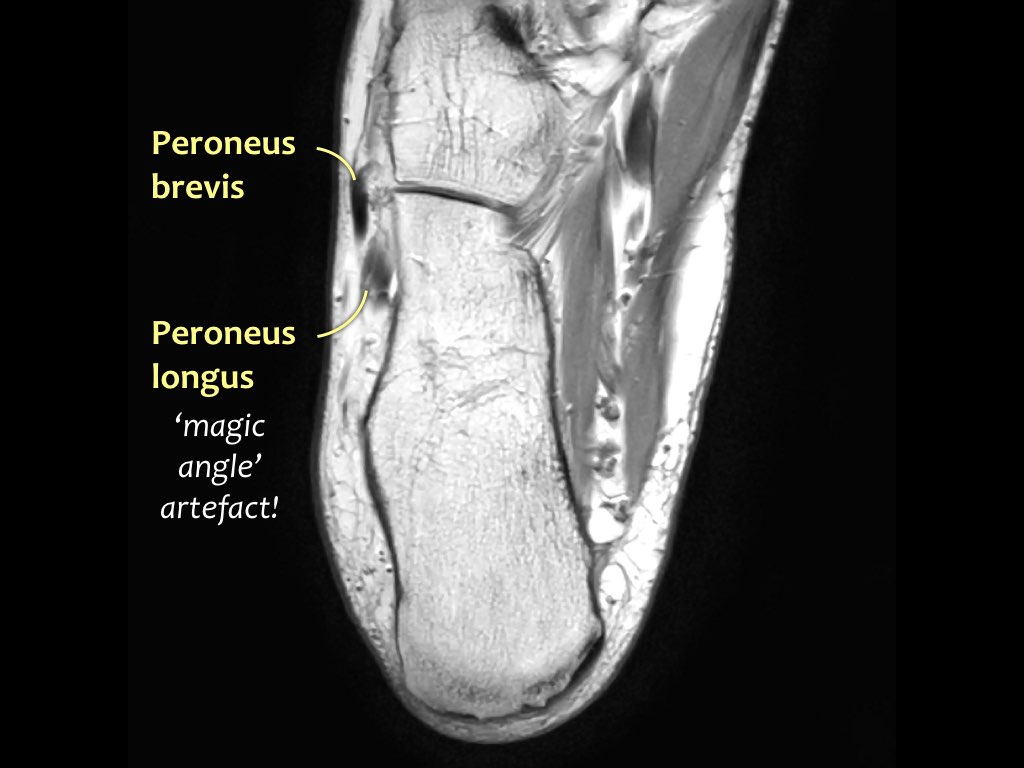

- Khoang ngoài

- Gân cơ mác dài (Peroneus Longus)

- Gân cơ mác ngắn (Peroneus Brevis)

Hướng đi của các gân dọc theo mắt cá trong và mắt cá ngoài có thể gây ra hiện tượng ‘xảo ảnh góc ma thuật’.

Các gân sẽ biểu hiện tín hiệu tăng tương đối khi tạo góc 55° so với B0, dễ nhầm lẫn với bệnh lý như viêm gân hoặc rách gân một phần.

Xảo ảnh này xuất hiện trên các chuỗi xung có thời gian TE ngắn (ví dụ: PD).

Trên các chuỗi xung có TE dài (như T2), xảo ảnh này cũng xuất hiện nhưng ít rõ rệt hơn.